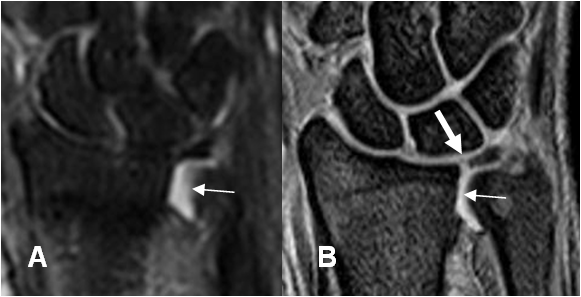

Fig 80. Degeneración del complejo del FCT.

A: RM coronal en T1 y B: RM coronal en STIR. Cartílago hipointenso en T1 e hiperintenso en STIR, hacia la inserción ulnar, por degeneración. Lesión tipo 2A.

Fig 81. Degeneración del complejo del FCT.

A: RM coronal en STIR. Lesión osteocondral en la ulna distal.

B: RM coronal en FFE y C: RM coronal en T1. Alteración en la señal del FCT, por degeneración. (Flechas delgadas). Existen lesiones osteocondrales en el semilunar y el piramidal. (Flechas gruesas), por lesión tipo 2B.